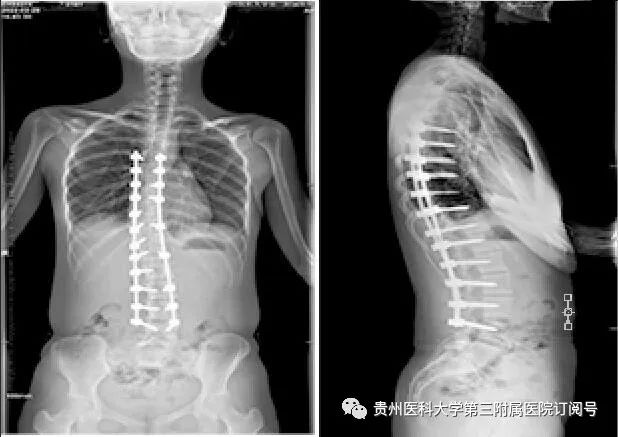

术前全脊柱正侧位片

2月22日,杨华、熊永发带领骨科团队为小玲顺利实施了“后路脊柱侧弯矫形手术”。术后,小玲侧弯脊柱得以矫正,身高还增高了约3厘米。